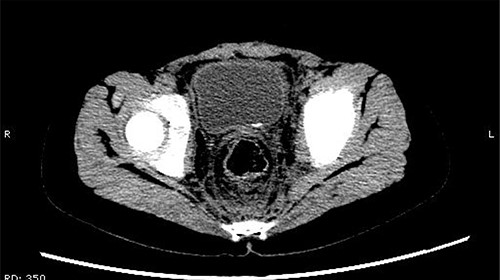

The patient was confined to bed, fasted and prescribed a daily intravenous infusion of cefazolin sodium pentahydrate, 2.0 g for 10 days. CT showed some irregular high-density shadows were present in the left renal pelvis (Fig. 1), and a small strip of high-density shadow was apparent in the bladder cavity (Fig. 2). Blood tests showed no abnormality in serum calcium concentration. Cefazolin sodium pentahydrate was discontinued immediately.

A small strip of high-density shadow was present in the bladder cavity.